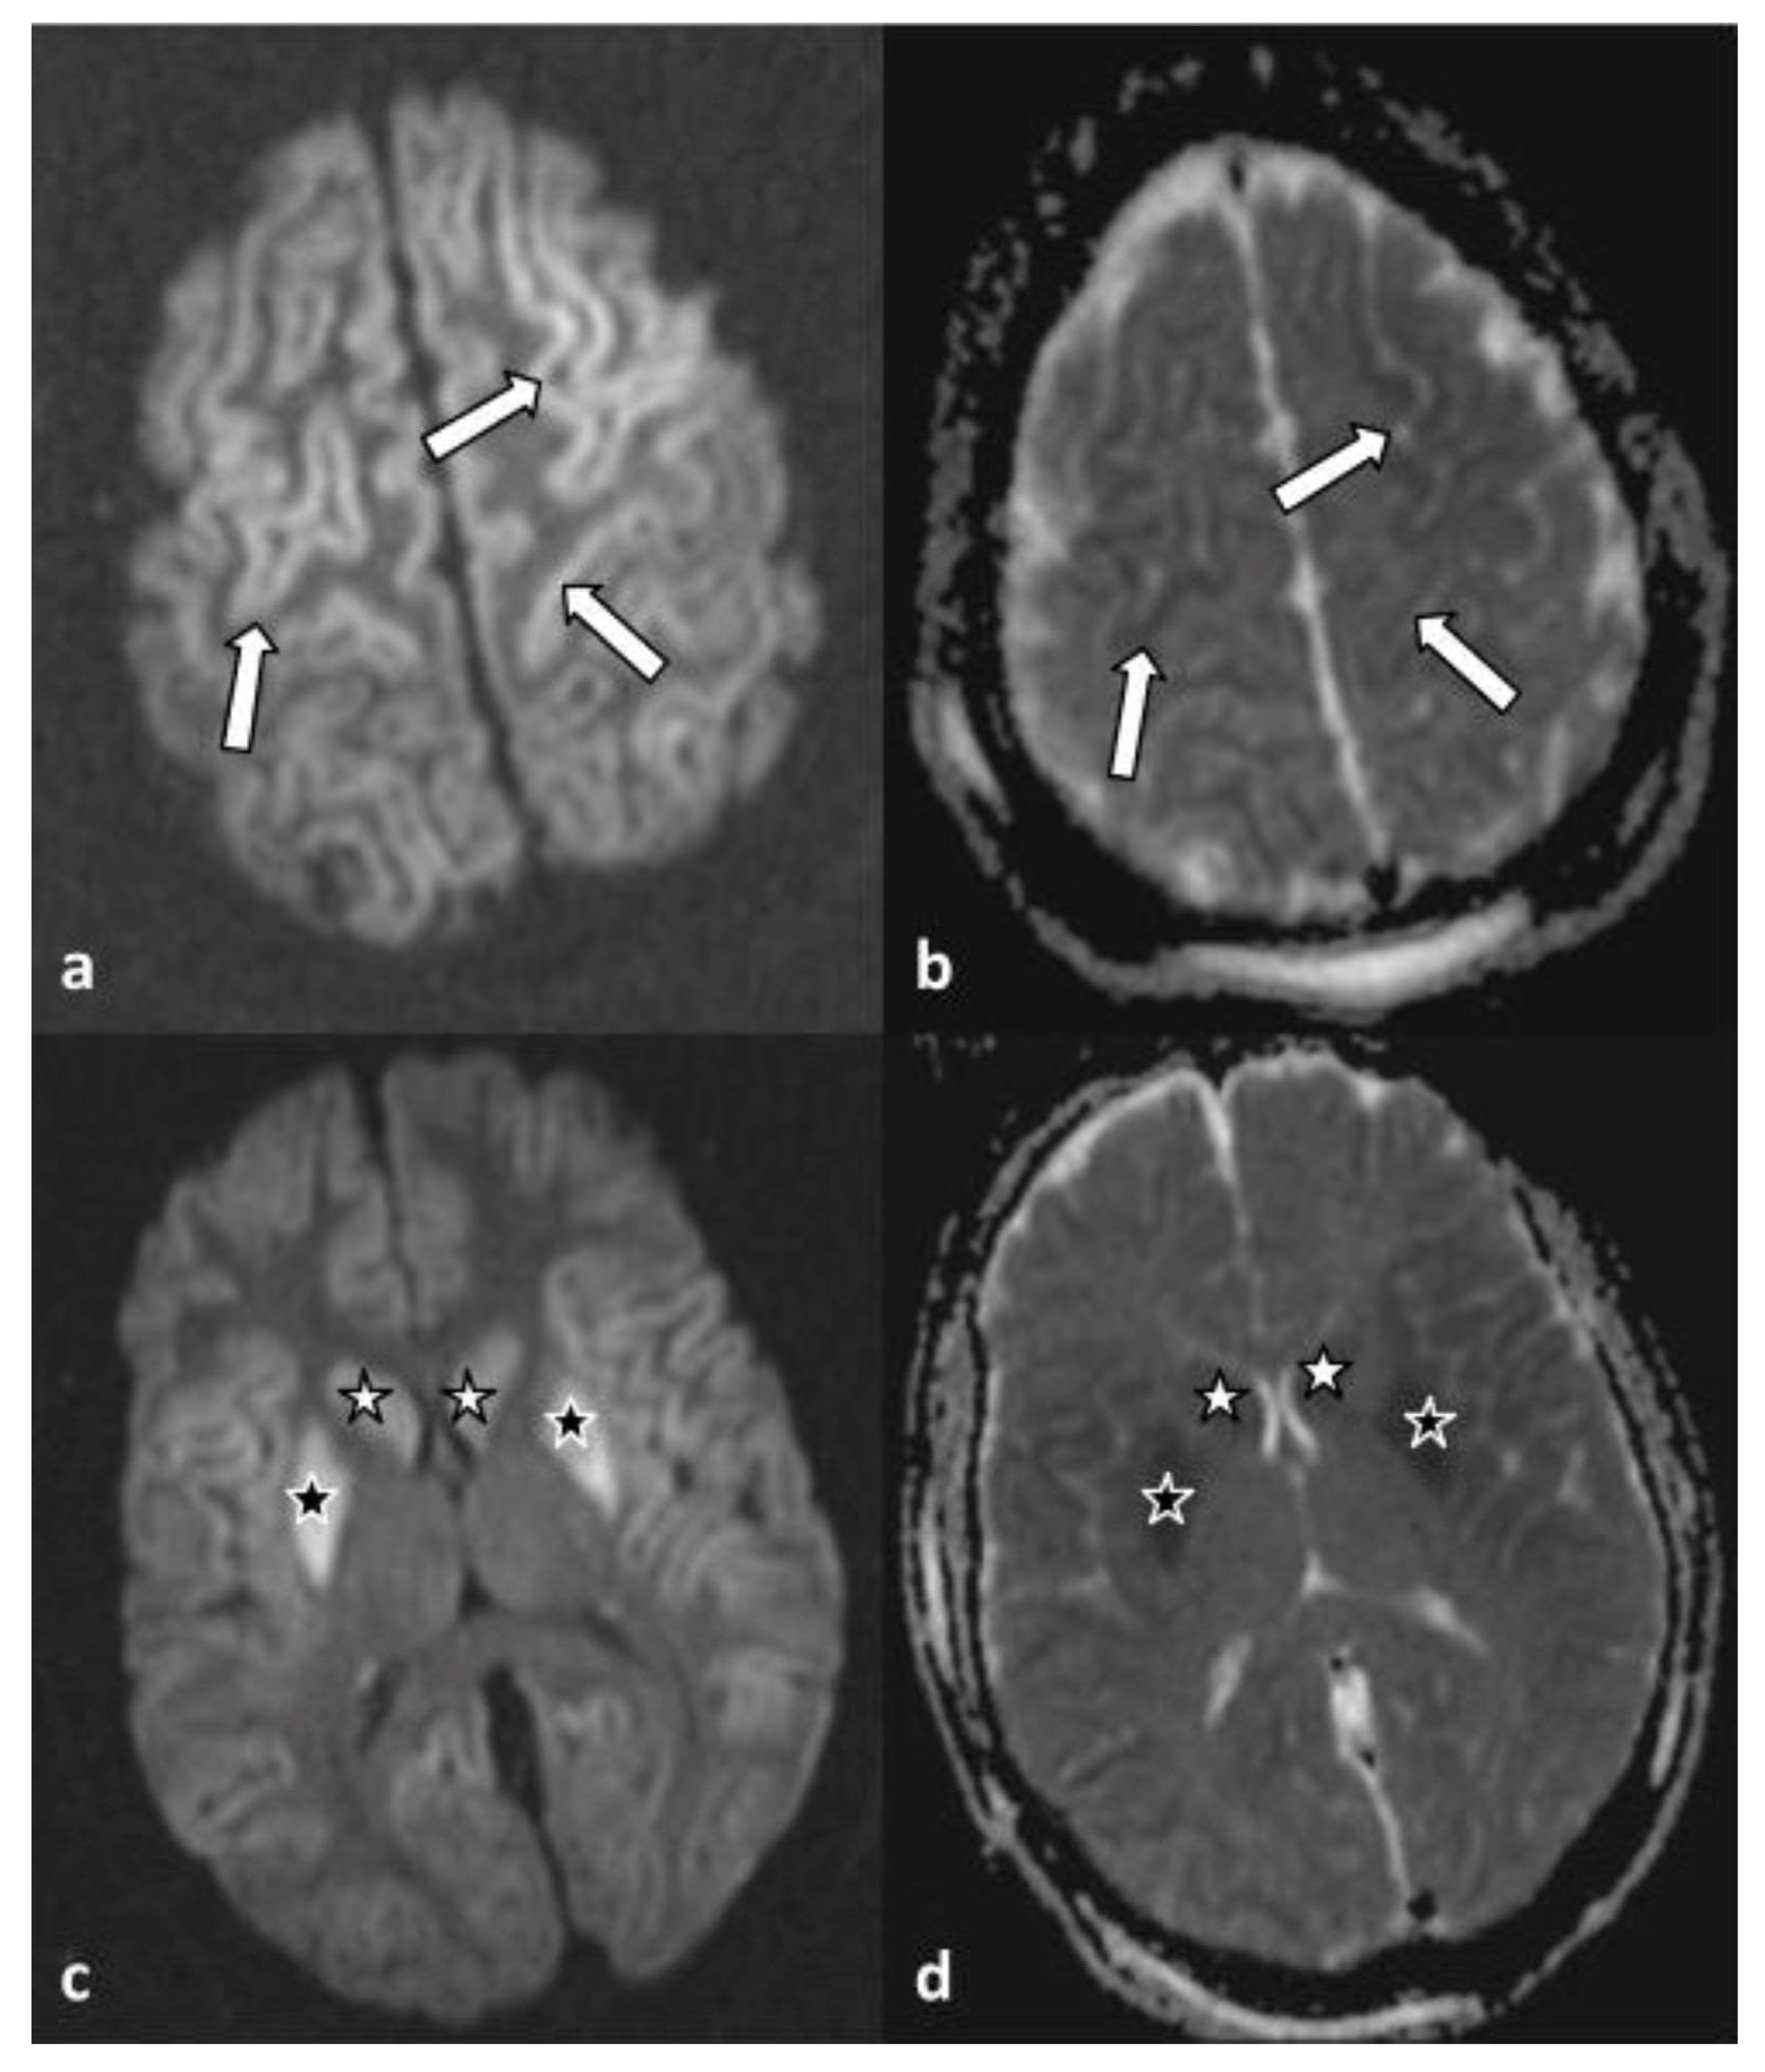

Moreover, infratentorial leptomeningeal enhancement, most prevalent along the anterior aspect of the temporal lobes (arrows), was observed in axial T1-weighted MR images without (a and c) and after (b and d) administration of intravenous contrast. The findings were suggestive of the presence of meningitis/meningoencephalitis (Figure 2).

Figure 2. Axial T1-weighted MR images without (a,c) and after (b,d) administration of intravenous contrast material. An infratentorial leptomeningeal enhancement was noted, most prevalent along the anterior aspect of the temporal lobes (arrows). The findings were suggestive of the presence of meningitis/meningoencephalitis.